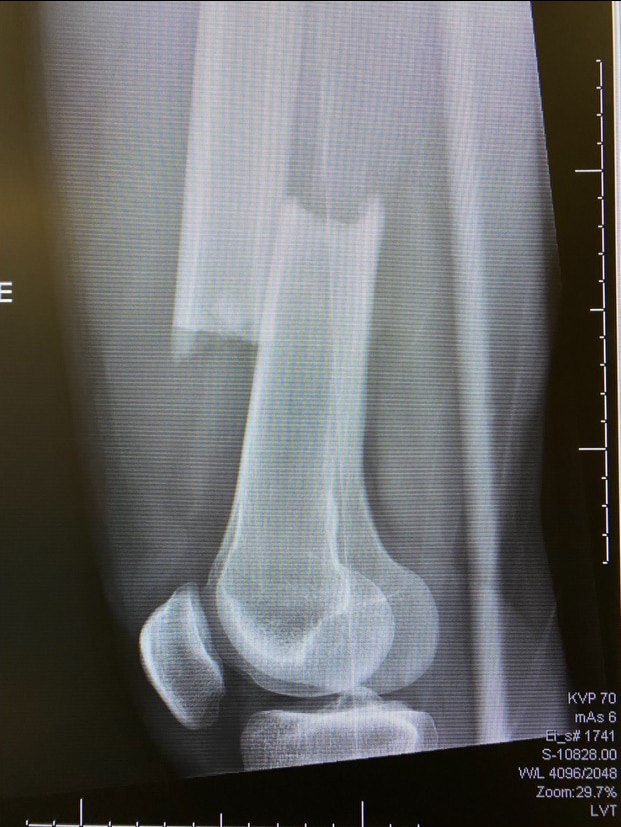

Easton Brodzinski's broken right femur. Easton Brodzinski's right femur was described as a clean break.

With a minute gone in the second period, Brodzinski skated the puck across the middle of the offensive zone. Eagles forward Trevor Kuntar hustled towards him from the opposite direction. The collision left Brodzinski on the ice, grabbing for his right leg. His femur was completely broken, a clean break.

Two hours later, he was in surgery at a local hospital getting a metal rod put in his leg.